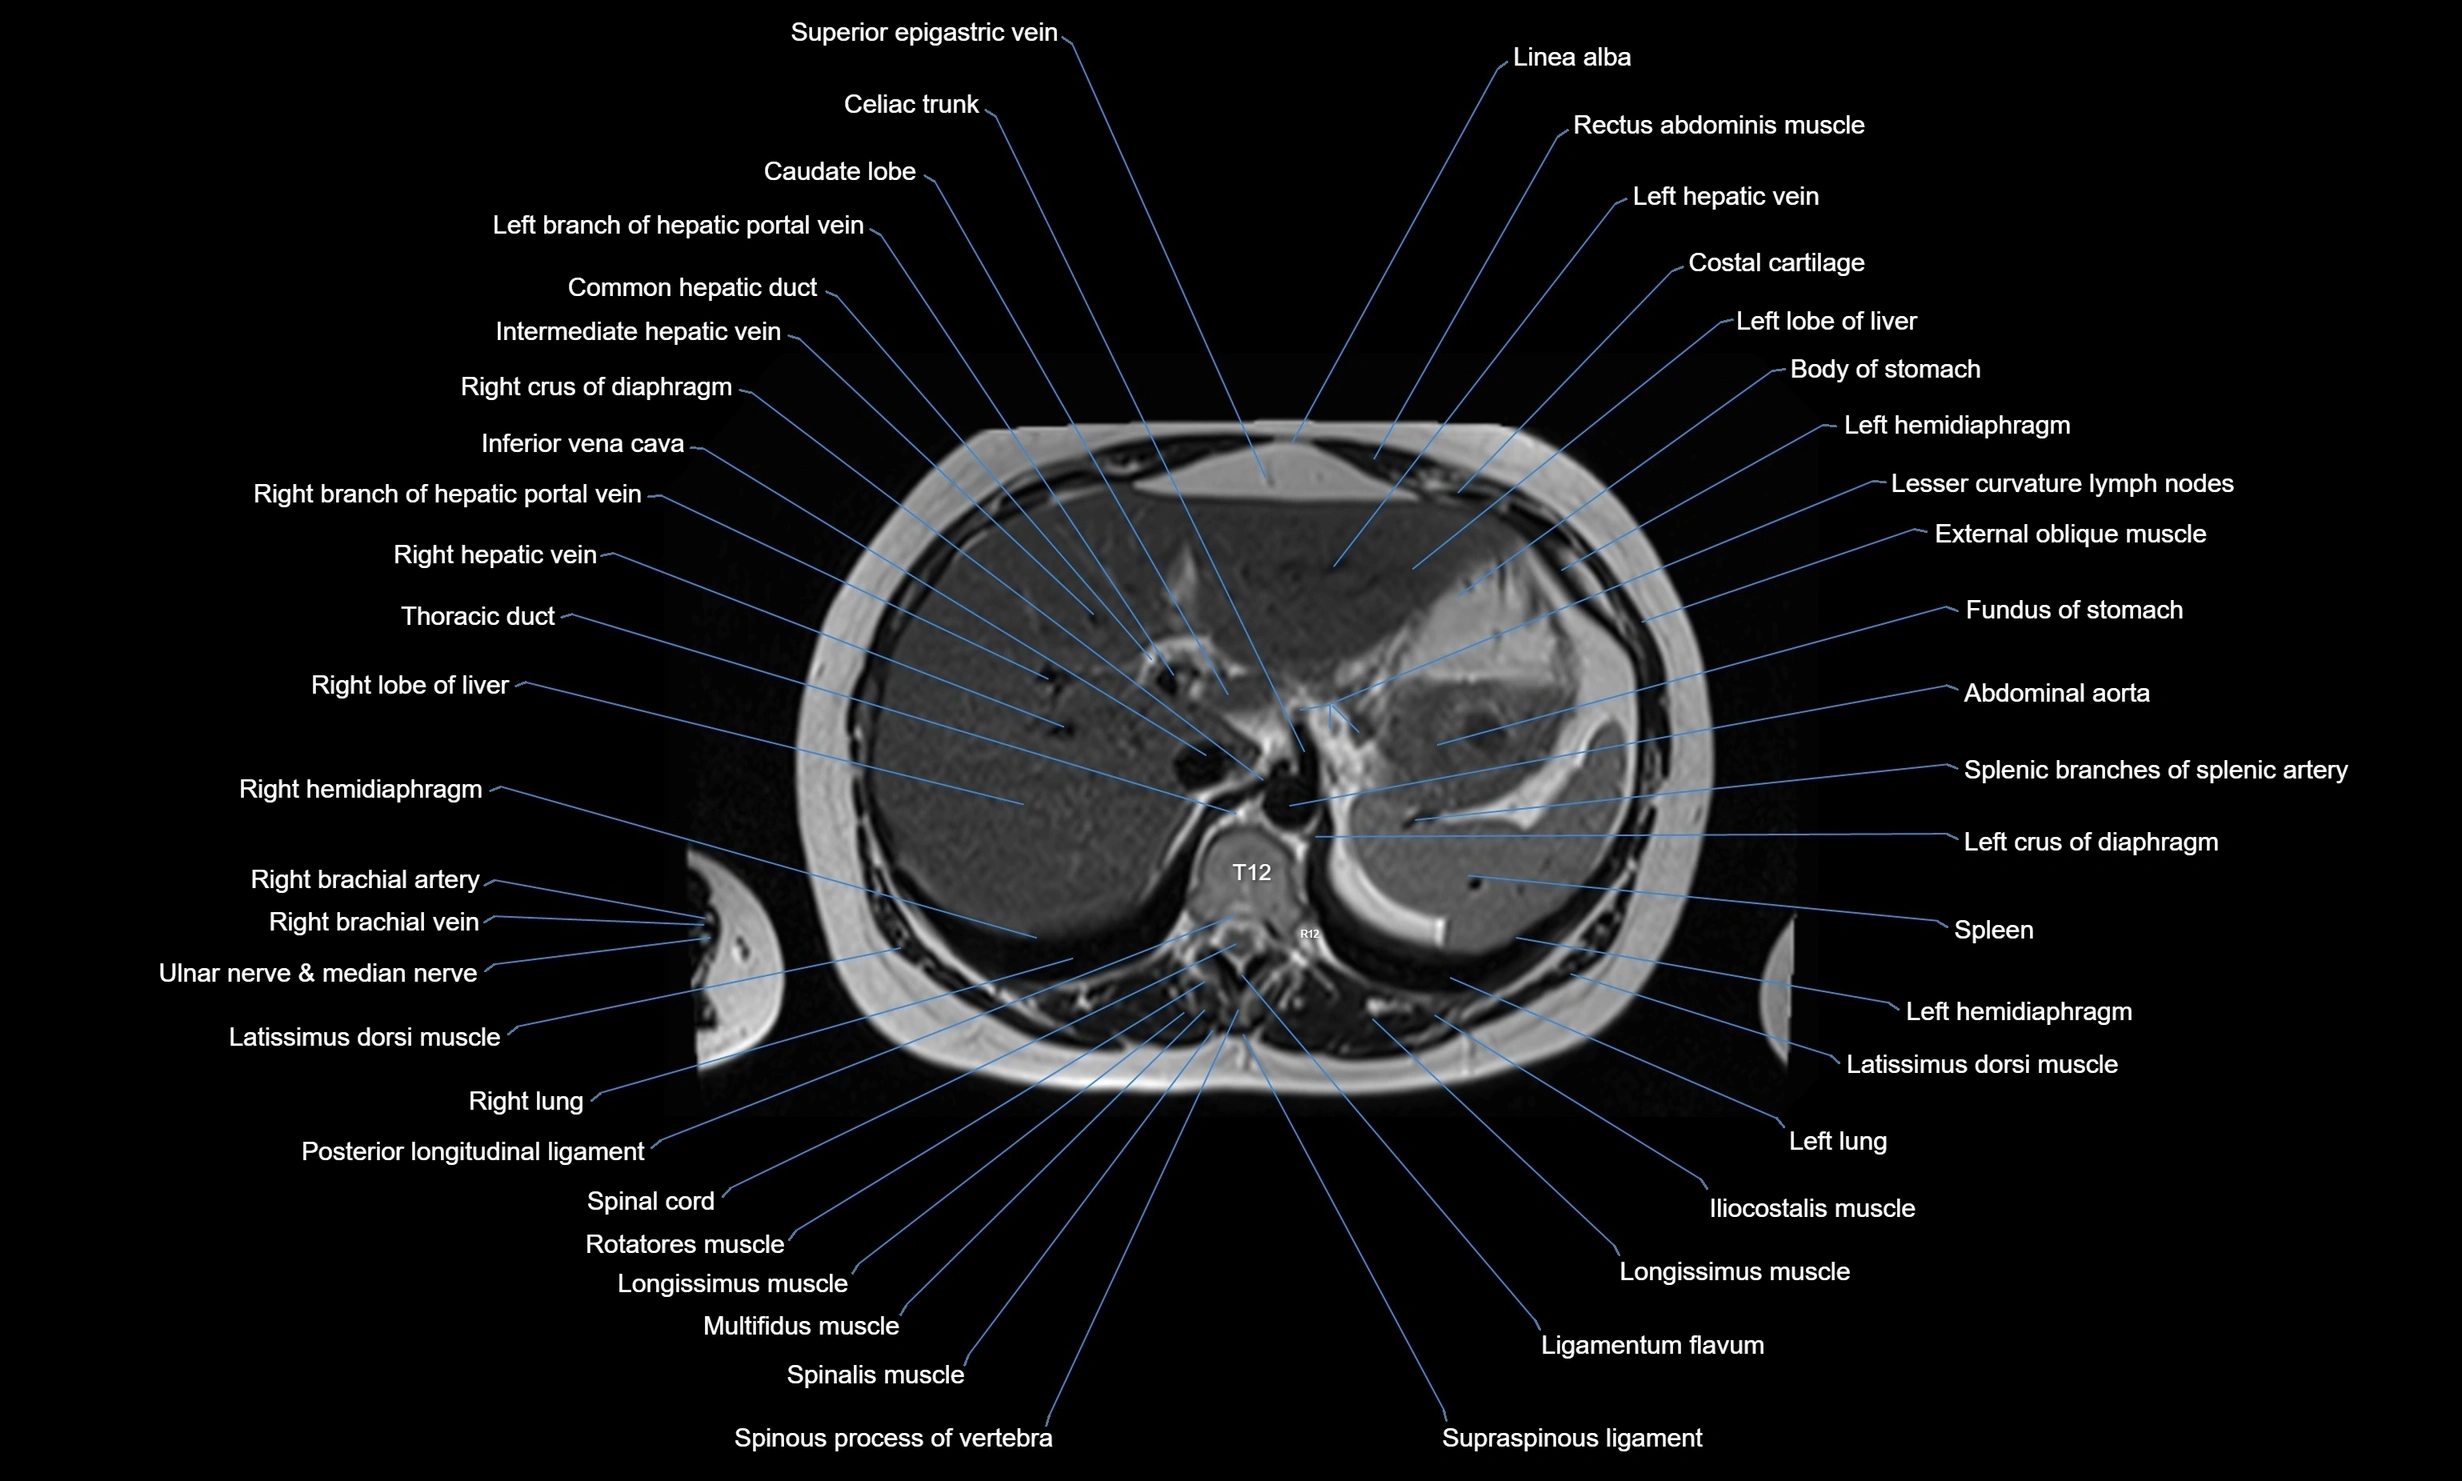

MRI images